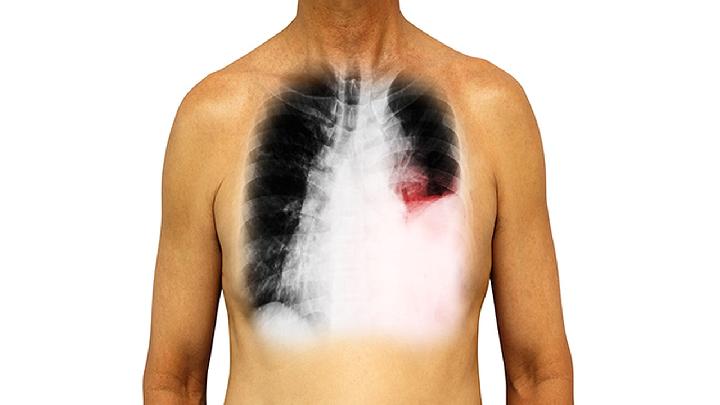

支气管镜是一种用于检查和治疗呼吸系统疾病的常用手段,主要用于检查气道、支气管和肺部。做支气管镜对肺的伤害包括出血、感染、支气管痉挛、气胸、肺部或其他结构损伤等。

4、气胸:在罕见情况下,支气管镜检查可能会导致气胸,即气体进入胸腔导致肺部受压缩,这种情况需要进一步处理和治疗。

5、肺部或其他结构损伤:在极少数情况下,支气管镜检查可能导致肺部或其他结构的损伤,如支气管壁的划伤或穿孔。这种情况通常是罕见的,但也需要进行相应的监测和治疗。